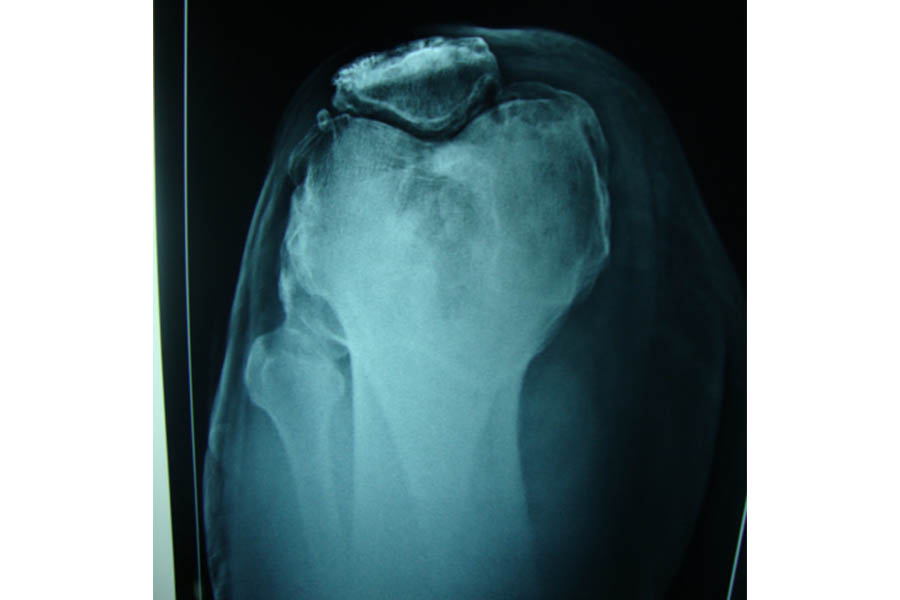

Total Elbow Replacement

Case 1